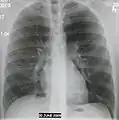

A chest X-ray showing a very prominent wedge-shape bacterial pneumonia in the right lung

The discovery of x-rays made it possible to determine the anatomic type of pneumonia without direct examination of the lungs at autopsy and led to the development of a radiological classification. Early investigators distinguished between typical lobar pneumonia and atypical (e.g. Chlamydophila) or viral pneumonia using the location, distribution, and appearance of the opacities they saw on chest x-rays. Certain x-ray findings can be used to help predict the course of illness, although it is not possible to clearly determine the microbiologic cause of a pneumonia with x-rays alone.